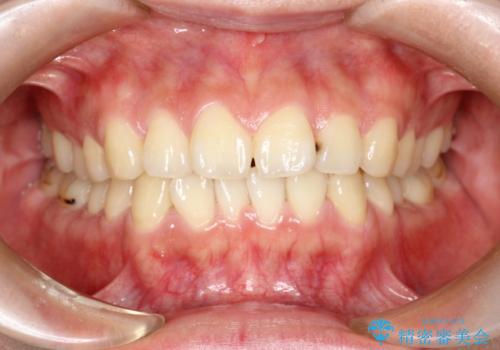

- 子供のころに矯正治療をされていたが、後戻りをしてしまったという20代女性の患者様です。上顎左右の2番が、咬合時に下顎の歯よりも内側に入っているクロスバイトという状態でした。奥歯の咬合関係は変えずに、マウスピース矯正にて前歯の並びを綺麗なアーチに仕上げました。再度後戻りしてしまうリスクを軽減させるために、リテーナー(保定装置)をお渡ししています。